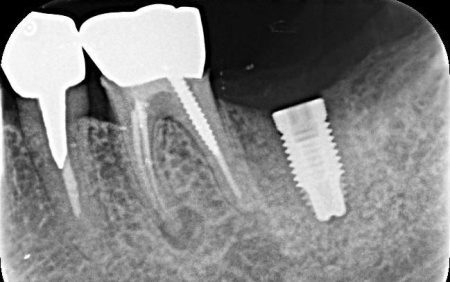

| 診断 | 拝見したところ、左下の一番奥の歯(第2大臼歯)の歯茎に腫れが認められました。 レントゲン撮影を行って詳しく調べたところ、歯根が縦方向に割れている「歯根破折」が疑われる状態です。 歯根破折は、過去に神経の治療を行った歯に起こりやすいトラブルで、今回のケースでは被せ物の下で破折が進行していたと考えられます。 このまま放置すると、痛みや腫れを繰り返すだけでなく、周囲の骨が溶けて隣接する歯にも悪影響を及ぼすおそれがあるため、抜歯の必要があると診断しました。 |

治療前

歯根破折が疑われました。